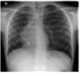

Dextroposition

Scimitar syndrome, or congenital pulmonary venolobar syndrome, is a rare congenital heart defect characterized by anomalous venous return from the right lung (to the systemic venous drainage, rather than directly to the left atrium). This anomalous pulmonary venous return can be either partial (PAPVR) or total (TAPVR). [Source: Wikipedia ]